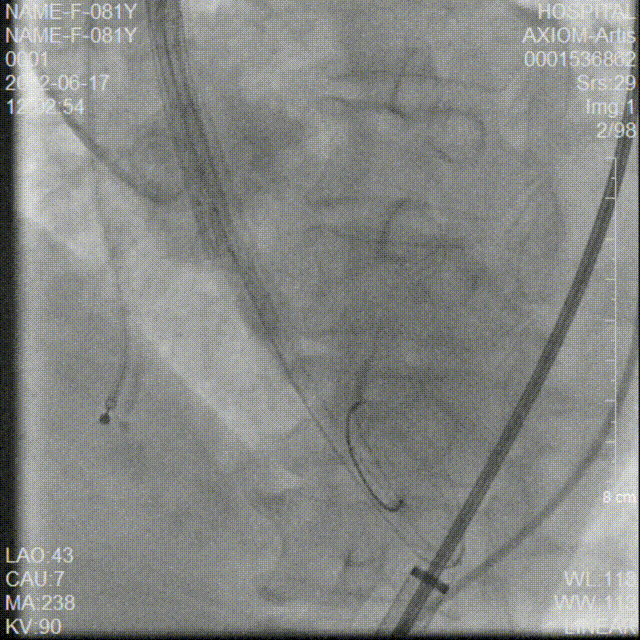

AV26瓣膜定位

AV26瓣膜第一次释放到工作位

第一次释放到工作位造影检查